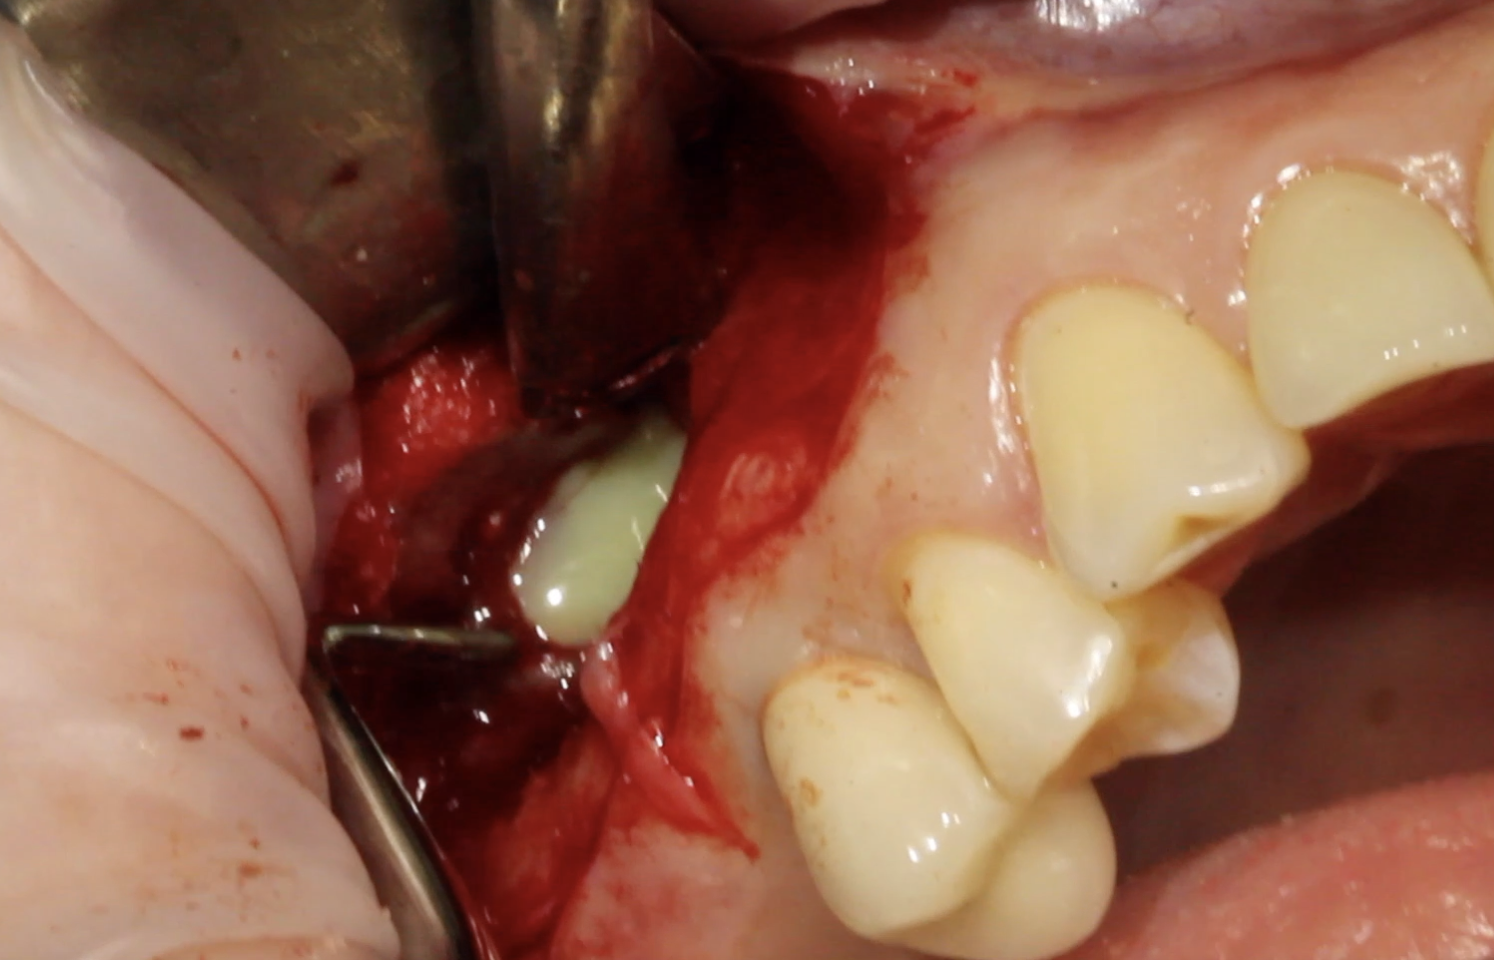

Имплантаияпри одновременном восстановлениигоризонтальных дефектов челюсти - не«сосидж»